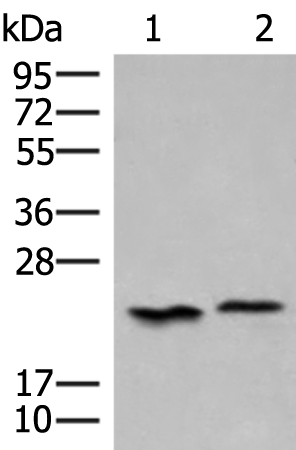

分类: 科研抗体货号: P13549别名: HAD; HCDH; HHF4; HADH1; SCHAD; HADHSC; MSCHAD应用: WB,IHC反应种属: Human, Mouse, Rat